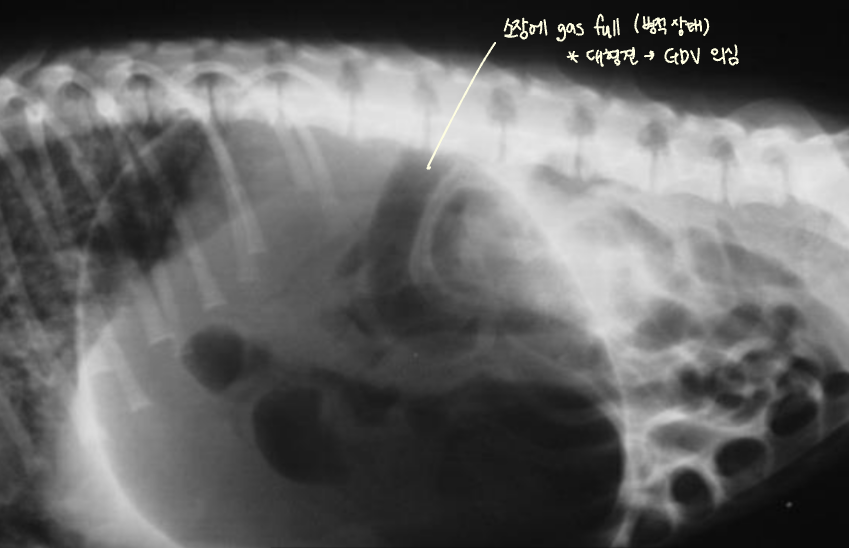

| GD | GDV | |

| VD | - greater curvature ์ผ์ชฝ(์ ์) * 360๋ ํ์ ์์๋ ์ผ์ชฝ์ ์์น | - greater curvature ์ค๋ฅธ์ชฝ (180๋ ์ผ์ ) - duodenum ์์น๋ ํจ๊ป ๊ผฌ์ |

| RL | - pylorus๊ฐ ์๋์ชฝ(์ ์) | - pylorus ์์ชฝ - ์์ ๋ถํํ(compartmentalization) : ๋ถ๋ฐฉ ํ์ธ - gastric band (soft tissue) ๊ด์ฐฐ |

![]() ![]() | ![]() ![]() | |

GDV

- ๋ฐฐ๊ฐ ๋นต๋นตํ๊ณ , ๊ณ ํต์ค๋ฌ์ ํ๋ฉด์ ๋ด์ํจ.

- ๋ํ๊ฒฌ์์ ์ ๋ฐ์ํจ. ์๊ธ ์์ ํ์.

- Serosal detail ๊ฐ์, ํ์ alveolar/interstitial pattern์ด ํจ๊ป ๊ด์ฐฐ๋๋ฉด ์ํ๊ฐ ์ ์ข์.